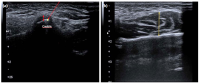

The probe was placed on the TMJ parallel to the long axis of the mandible in an upright sitting position, with their heads free. For both right and left TMJ with the mouth closed; between the condyle and the fossa; a hypoechogenic thin band-shaped area was measured and noted as a disc gap (Figure 2a).

During the USG examination, the effusion displayed as a hypoechoic area in the joint cavity on bilateral TMJ, irregularity on the bone surface, the presence of osteophytes, which are seen as hyperechoic new bone formations with exophytic extension, were evaluated and recorded on the examination form as present or absent. In the TMJ evaluation, flattening and irregularity in bone structures were noted as temporal bone or condyle degeneration.